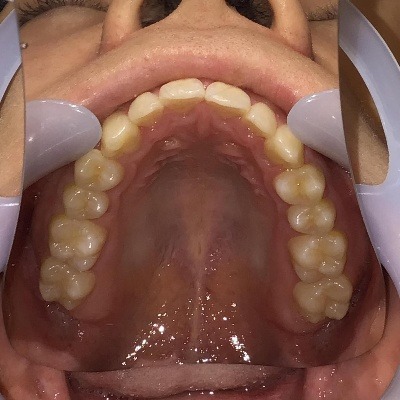

上顎

| 治療内容 | インビザライン 全顎 |

| 治療詳細 | 反対咬合や叢生を整えるために、歯の表面にアタッチメント(白い突起)をつけ、IPR(歯と歯の間を削る)を行いました。 また、顎間ゴムと呼ばれる上顎と下顎に渡って引っ掛けるゴムの補助装置も用いて治療を行いました。 |

| 患者情報 | 10代 男性 デンタルモニタリング使用 |

| 主訴 | 下顎が前に出ている(受け口) 歯のがたつき |